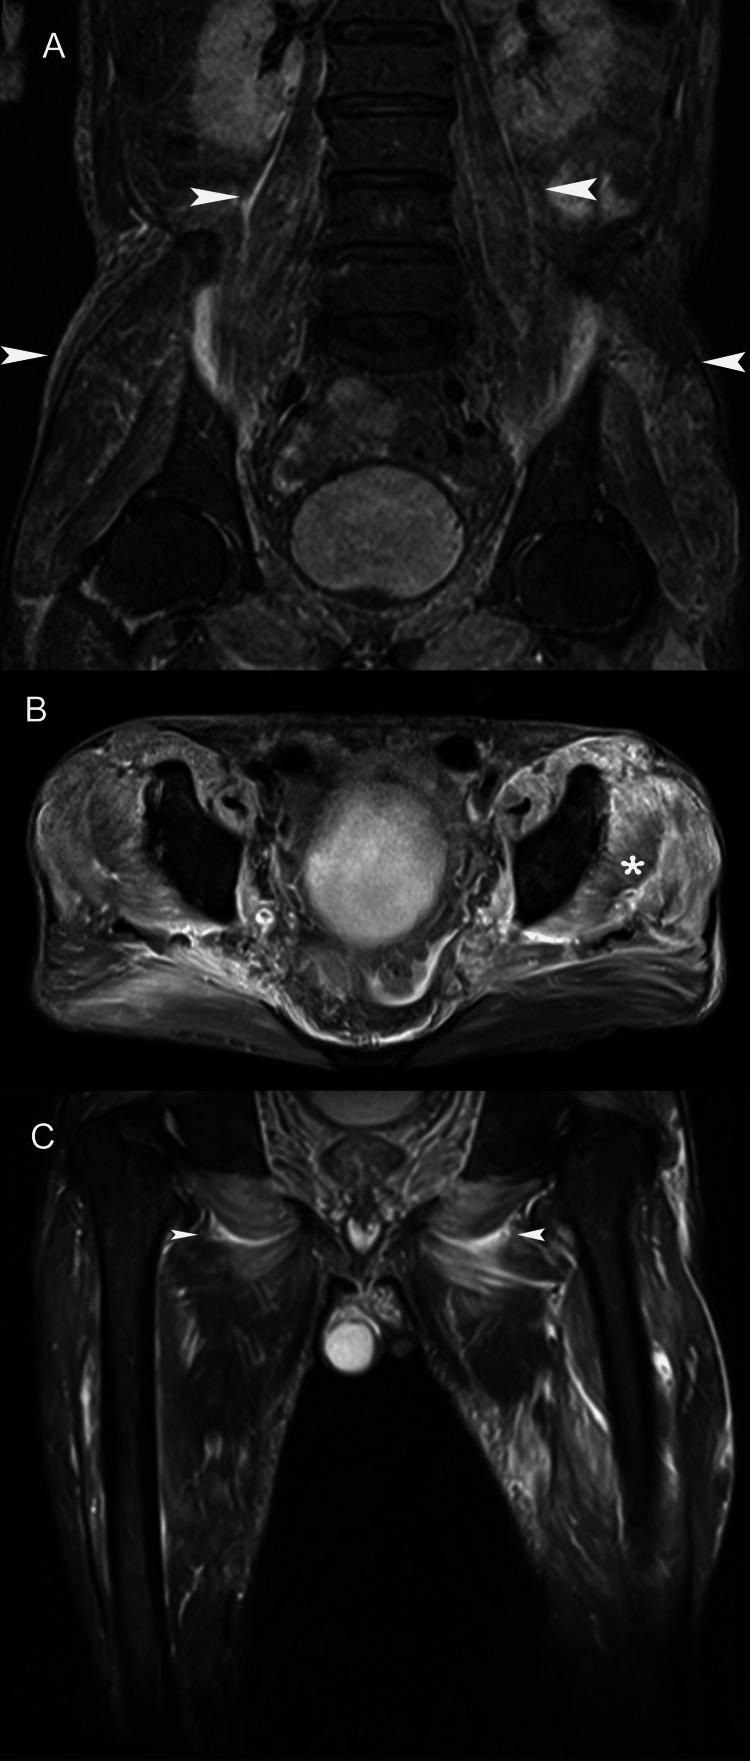

Skeletal muscle is a major anatomic structural component of the human body. Myopathy, defined as skeletal muscle disease, may offend any of the body's 650 muscles and encompasses an extended array of acute and chronic abnormalities. Muscle disease can be categorized according to etiology as congenital, traumatic, infectious, or neoplastic. The concept of the diversity of multiple muscular disease processes signifies an important role for imaging in the detection and characterization of myopathy. However, despite the exquisite physiological properties of skeletal muscle, muscle imaging has not received attention equal to that of bones and joints. Accordingly, this article provides an indication of the most suitable imaging modalities for myopathy and reviews a multitude of primary and systemic muscle derangements, with an emphasis on magnetic resonance (MR) imaging findings. Because these patterns of MR imaging abnormality bespeak the widespread nature of myopathy, we illustrate typical examples of muscle disease processes to simplify diagnosis.

骨骼肌是人体主要的解剖结构组成部分。肌病,定义为骨骼肌疾病,可累及人体650块肌肉中的任何一块,涵盖一系列急性和慢性异常情况。肌肉疾病可根据病因分为先天性、创伤性、感染性或肿瘤性。多种肌肉疾病过程的多样性概念表明成像在肌病的检测和特征描述中具有重要作用。然而,尽管骨骼肌具有精细的生理特性,但肌肉成像并未得到与骨骼和关节成像同等的关注。因此,本文指出了最适合用于肌病的成像方式,并综述了多种原发性和全身性肌肉紊乱,重点关注磁共振(MR)成像表现。由于这些MR成像异常模式表明肌病具有广泛的性质,我们展示了肌肉疾病过程的典型例子以简化诊断。